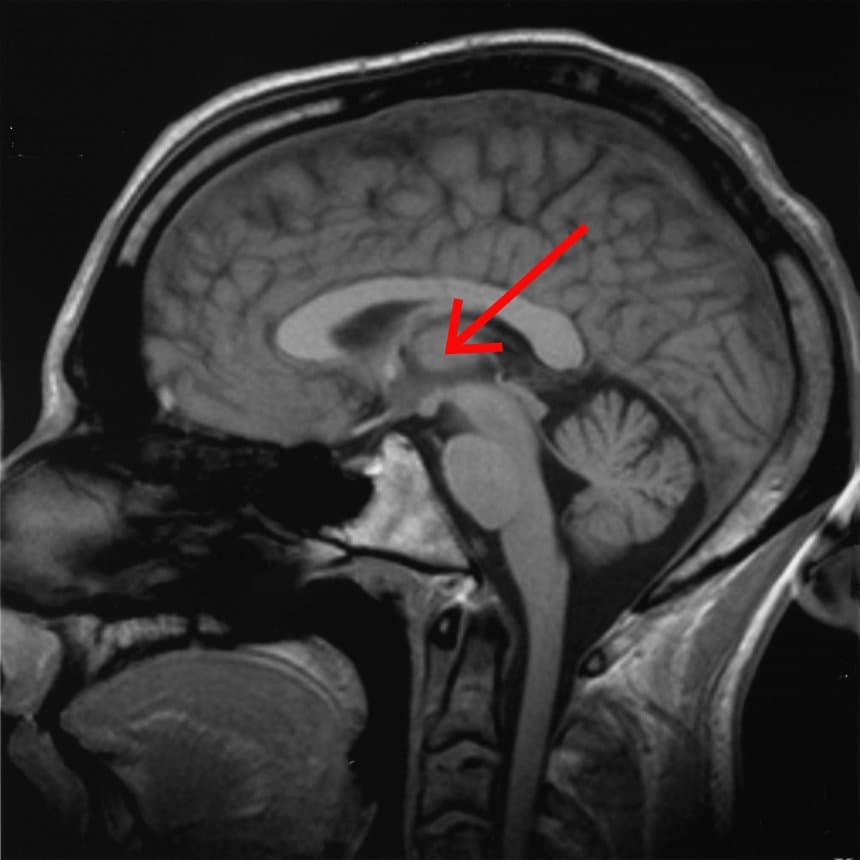

The thalamus (from Greek θάλαμος, "chamber") is a large mass of gray matter located in the dorsal part of the diencephalon (a division of the forebrain). Nerve fibers project out of the thalamus to the cerebral cortex in all directions, allowing hub-like exchanges of information. It has several functions, such as the relaying of sensory signals, including motor signals to the cerebral cortex and the regulation of consciousness, sleep, and alertness. Anatomically, it is a paramedian symmetrical structure of two halves (left and right), within the vertebrate brain, situated between the cerebral cortex and the midbrain. It forms during embryonic development as the main product of the diencephalon, as first recognized by the Swiss embryologist and anatomist Wilhelm His Sr. in 1893. The thalamus is a paired structure of gray matter located in the forebrain which is superior to the midbrain, near the center of the brain, with nerve fibers projecting out to the cerebral cortex in all directions. The medial surface of the thalamus constitutes the upper part of the lateral wall of the third ventricle, and is connected to the corresponding surface of the opposite thalamus by a flattened gray band, the interthalamic adhesion. The lateral part of the thalamus is the phylogenetically newest part of the thalamus (neothalamus), and includes the lateral nuclei, the pulvinar and the medial and lateral geniculate nuclei. There are areas of white matter in the thalamus including the stratum zonale that covers the dorsal surface, and the external and internal medullary laminae. The external lamina covers the lateral surface and the internal lamina divides the nuclei into anterior, medial and lateral groups. The thalamus derives its blood supply from a number of arteries: the polar artery (posterior communicating artery), paramedian thalamic-subthalamic arteries, inferolateral (thalamogeniculate) arteries, and posterior (medial and lateral) choroidal arteries. These are all branches of the posterior cerebral artery.